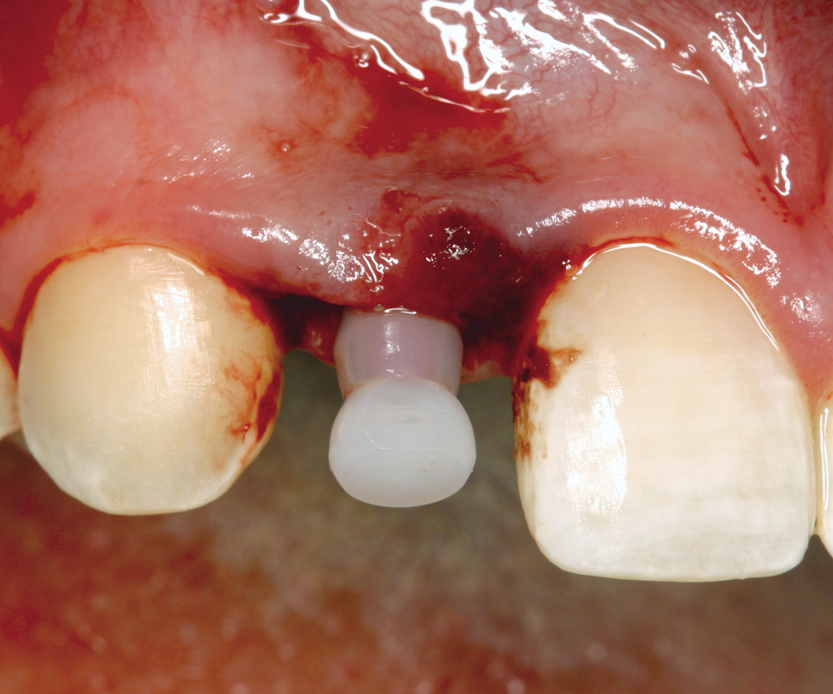

Fig 7. Six weeks postoperative, after autotransplantation of tooth No. 20 into site No. 9.

Figure 7

A less commonly used but highly effective method of replacing lost anterior teeth is autotransplantation.18 A common indication for autotransplantation is the replacement of a missing maxillary anterior tooth with a mandibular second premolar. (A case example is shown in Figure 5 through Figure 10.) Timing of the surgery is critical. Orthodontic treatment must be timed so that the recipient site is ready when the donor tooth has two-thirds to three-fourths root development. Measurements must be made to ensure that the crown width of the donor tooth is comparable to the contralateral incisor of the tooth being replaced.

A socket is surgically created in the recipient site, and the donor tooth is atraumatically extracted; the entire dental follicle must be intact and undamaged. The donor tooth is placed in the newly created socket. There must be no pressure on the periodontal ligament, and the transplanted tooth must be out of occlusion. The tooth is stabilized for 6 weeks with a light orthodontic wire. As the tooth matures, it may erupt normally; however, orthodontic treatment is frequently required to move the tooth into the correct position for restoration.